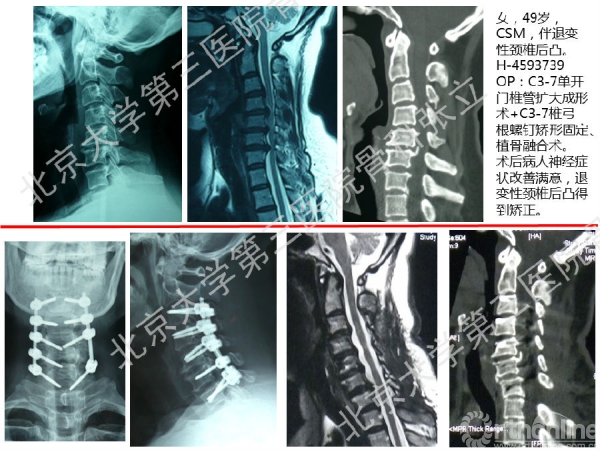

徒手置钉的下颈椎椎弓根钉技术对于很多骨科同道来说,无疑是难度超高、不敢触及的一项技术。已熟练掌握这一技术的北京大学第三医院骨科张立主任医师认为,下颈椎椎弓根钉徒手置钉技术固定可靠,能满足绝大多数后路固定所需,可应用于脊柱外伤、脊柱畸形、脊柱肿瘤,以及CSM伴退变性颈椎后凸畸形。它的优势是:螺钉尾部靠外,不影响椎板成形术;先置钉固定,后开门,更安全;和椎板成形术完美结合,减压、复位、固定一次完成;极少出现脊髓、神经根及椎动脉损伤。